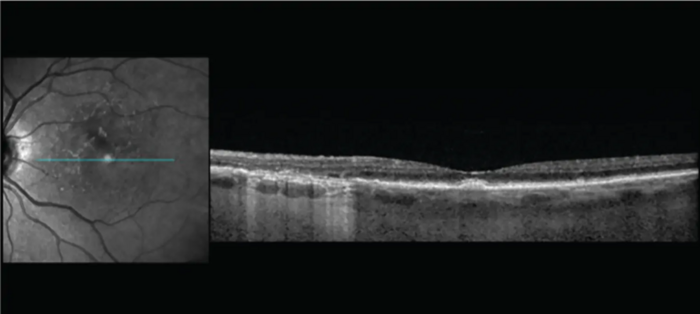

High-resolution imaging provides clear details of early degeneration of the outer retina.

Image courtesy: Jeremiah Brown, Jr, MD